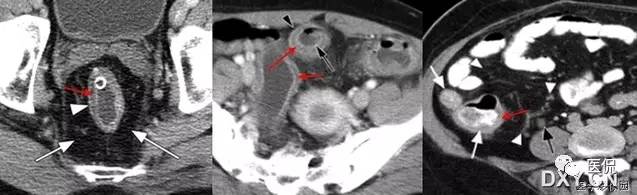

19 珍珠项链征又名珍珠项圈征

【影像表现】在CT或MRCP及T2W I上增厚的胆囊壁中多发、微小圆点状的高信号囊腔,大小2~7mm,一般为4mm,形似珍珠项圈。

【征象解释】胆囊肌层及上皮增生、肥大,粘膜外翻进入肌层形成罗-阿氏窦。因为罗-阿氏窦内充满胆汁,在MRCP或T2WI增厚的胆囊壁内可呈显著高信号点。

CT及MRI可发现胆囊壁的局限性或弥漫性增厚,以及病变处勒膜层的早期强化和浆膜层的延迟强化,但很难与胆囊炎和胆囊癌相鉴别。罗-阿氏窦内含胆汁,在T2WI上表现为胆囊壁肿块内或增厚的胆囊壁内直径为4~7mm的类圆形高信号灶;在动态增强扫描图像上,表现为增强的肿块内或增厚的胆囊壁内不强化的低或无信号灶。由于动脉期CT或MRI增强比较低的对比度与空间分辨率,较多小的罗-阿氏窦无法显示,动脉期CT或MRI能鉴别最小直径5mm的罗-阿氏窦,而MRCP能鉴别的最小直径是3mm,MRI重T2加权快速自旋回波序列在胆囊腺肌瘤病中的诊断价值已经被研究,因为罗-阿氏窦充满胆汁,在增厚的胆囊壁中可呈显著高信号点。单次激发快速SE序列MRCP很少出现运动伪影和磁敏感性伪影,对于显示罗-阿氏窦,单次激发快速自旋回波序列MRI比动脉期CT或MRI增强扫描及重T2加权快速自旋回波序列更可靠。

珍珠项链征在诊断胆囊腺肌瘤病方面特异性较高,达92%。因此,在诊断胆囊腺肌瘤病和鉴别胆囊腺肌瘤病与胆囊癌中是较为特异性的。MRCP对于显示<3mm的罗-阿氏窦有一定困难。胆囊囊壁内钙化在CT上能帮助诊断胆囊腺肌瘤病,而在MRCP上可能成为一个陷阱。浓胆汁比正常胆汁有更短的T1时间,浓胆汁患者罗-阿氏窦可能无法鉴别。因此珍珠项链征在这些患者中不能被鉴别,特别是用长回波时间的MRCP技术。浓胆汁T1时间短,在T1W I中显示为高信号强度。因此T2W I可能对证明罗-阿氏窦有帮助。因为胆囊壁内脓肿或黄色肉芽肿的存在。黄色肉芽肿性胆囊炎可能显示类似的珍珠项链征。胆囊腺肌瘤病与胆囊癌有时可以共存,员然很少见,但有这样的病例限制了珍珠项链征鉴别胆囊腺肌瘤病与胆囊癌。因此,那些局部胆囊腺肌瘤病的患者特别要密切随访检查,即使在MRCP图像上已明确异示珍珠项链征。